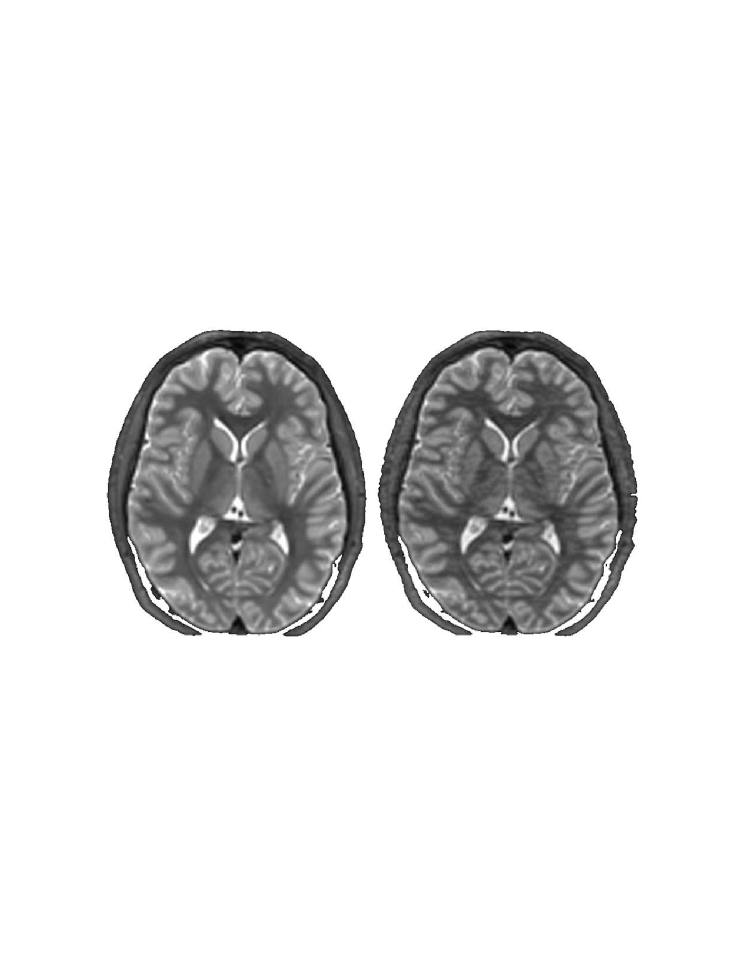

In this thesis, a novel coherent integrated methodology is introduced (theory, algorithm and applications) to reduce the dimensionality of high-dimensional datasets. The method constructs a diffusion process among the data coordinates via a random walk. The dimensionality reduction is obtained based on the eigen-decomposition of the Markov matrix that is associated with the random walk. The proposed method is utilized for: (a) segmentation and detection of anomalies in hyper-spectral images; (b) segmentation of multi-contrast MRI images; and (c) segmentation of video sequences.

This thesis is composed of three parts. In the first part, we introduce the novel Diffusion Bases methodology (theory, algorithms and applications) for dimensionality reduction. Specifically, in Chapter 2 we give an in depth introduction to dimensionality reduction where we provide a formal definition of the problem followed by a description of the current state-of-the-art techniques for dimensionality reduction. In Chapter 3 we describe in details the diffusion maps technique [45] since it is closely connected to our diffusion Bases (DB) dimensionality reduction scheme which we introduce in Chapter 4. The DB algorithm explores the variability among the coordinates of the original data while the DM explores local neighborhoods of points in the dataset. Both algorithms use a random walk model. The DB algorithm uses the eigenvectors of the corresponding Markov matrix as an orthonormal system and projects the original data onto it to obtain the low-dimensional representation. The DM algorithm, on the other hand, builds a different Markov matrix whose eigenvectors constitute the low-dimensional representation. In Chapter 5 we provide an introduction to hyper-spectral imagery which includes the terminology, concept, motivation and common applications in this area. Chapter 5 is necessary for the understanding of Chapters 6 and 9. Chapters 6-8 include successful applications of the DB scheme. Specifically, in Chapter 6, the DB dimensionality reduction scheme is used for segmentation of hyper-spectral images and for the detection of anomalies in images of this type. In Chapter 7, the DB scheme is incorporated in an algorithm for segmentation of multi-contrast MRI images. Segmentation of video sequences which uses the DB scheme is described in Chapter 8.

Some algorithms, which are used for specific image processing tasks such as segmentation, can be extended to handle hyper-spectral data volumes. The normalized cuts algorithm [197] can be extended in a straight forward manner to handle hyper-spectral data. However, this method uses a pixel similarity matrix without attempting to reduce the dimensionality of the data, which renders it to be computational expensive. Furthermore, the choice of pixel similarity metrics can be further investigated to yield better results.

6.3 The wavelength-wise global (WWG) algorithm for